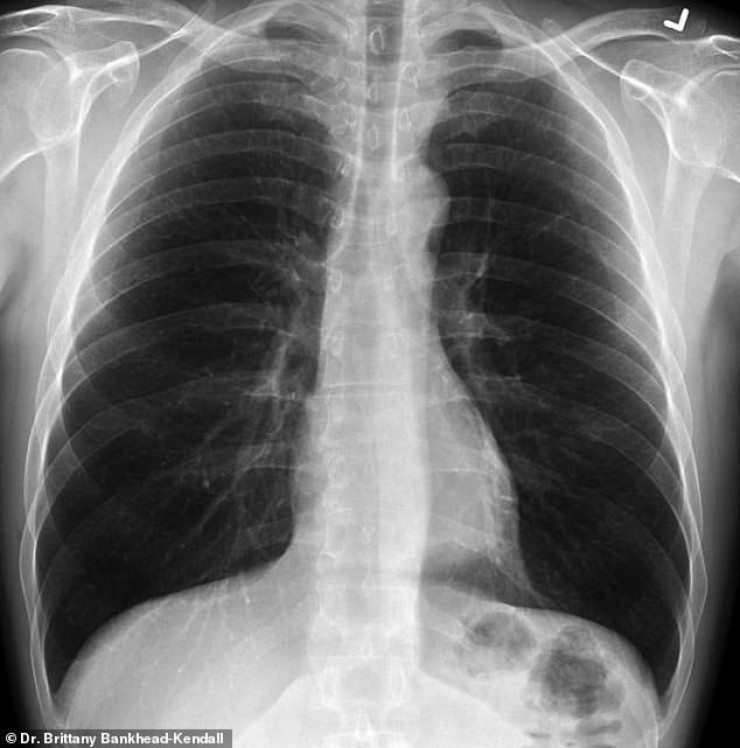

На рентгеновском снимке здорового пациента много черного пространства, что является показателем нормального количества кислорода.